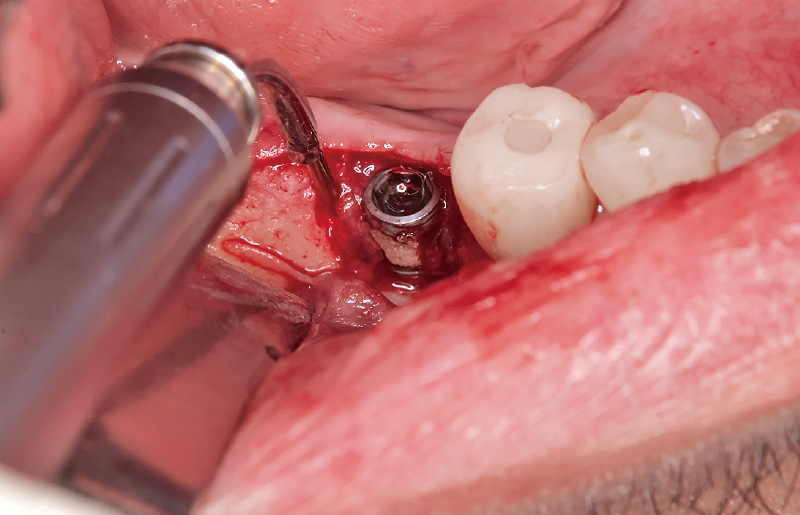

図4 「歯石除去」モードを用い、インプラント体に非接触でデブライドメントを行った。マイクロスコープ下の拡大視野において、一層のインプラント表面を慎重に削り取るイメージで処置を行うことが重要であり、拡大視野による精密操作が治療の成否を左右する。 -

![[写真] デコルチケーションを施行](/academic/dentalmagazine/wp-content/uploads/sites/2/2026/04//196-2_photo05.jpg)

図5 インプラント周囲炎により硬化性骨炎が生じ、骨への血液供給が期待できないため、デコルチケーションを施行した。その際、骨温度の上昇は4℃に留まり、熱による損傷は認められない。 -